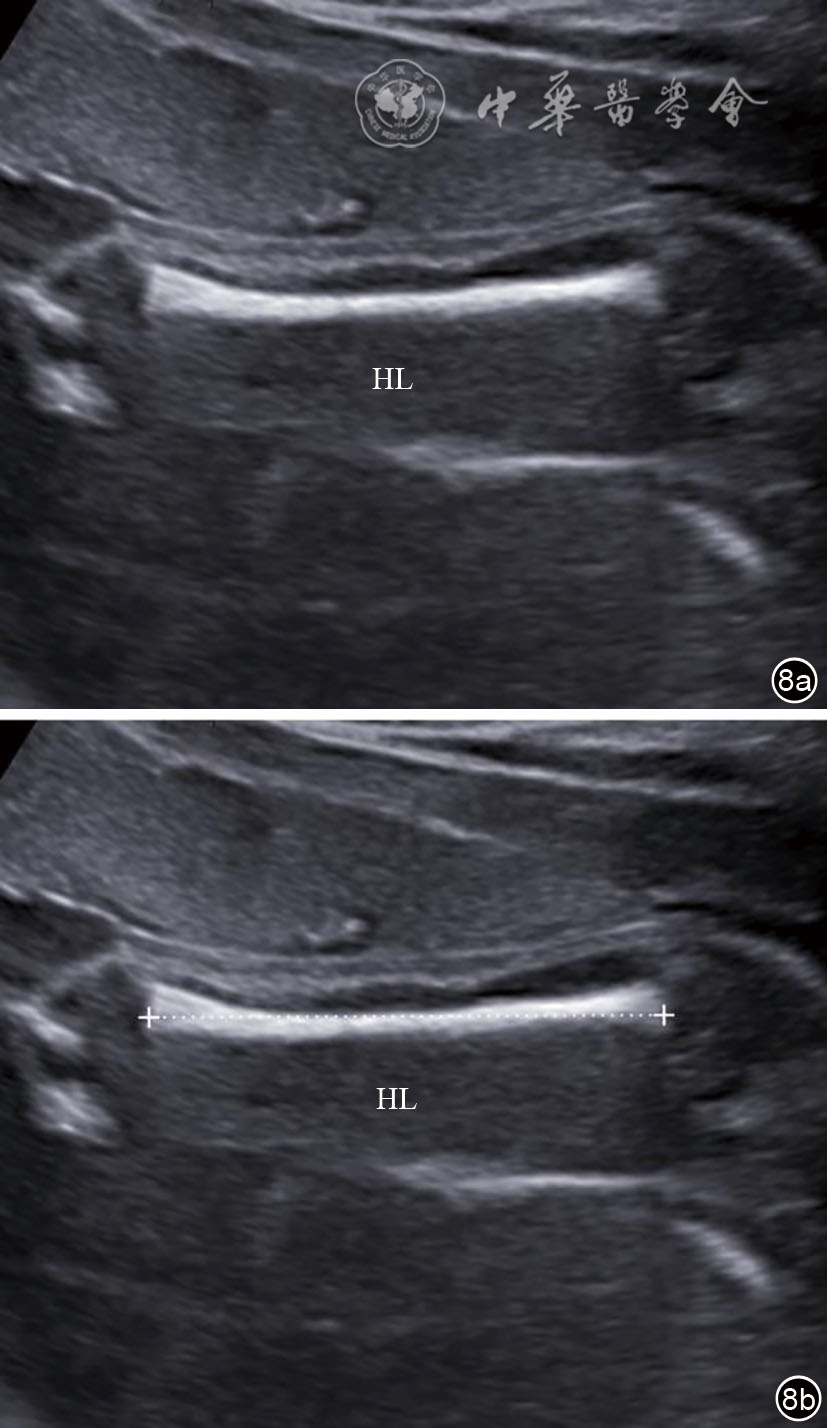

图8 肱骨长轴切面及肱骨长度测量超声图像。图a为肱骨长轴切面;图b为肱骨长度测量图 注:HL为肱骨